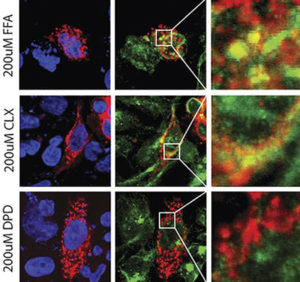

Alti livelli di ferro nei polmoni aumentano la gravità dell’asma

Un nuovo studio pubblicato sull’European Respiratory Journal nel marzo 2020 riporta che l’accumulo di ferro nelle cellule del polmone aggrava…